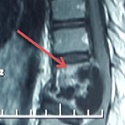

Une compression médullaire révélant une hydatidose vertébro-médullaire

Toufik Joulali , Mohammed Khatouf

PAMJ. 2013; 16: 113. Published 23 November 2013